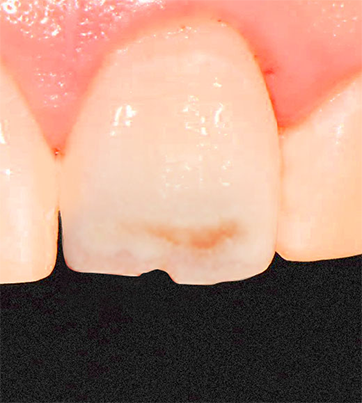

초기 충치 치료의 최선의 선택

레진 치료

치아색과 동일한 재료로 자연스럽게 복원하는 치료법입니다.